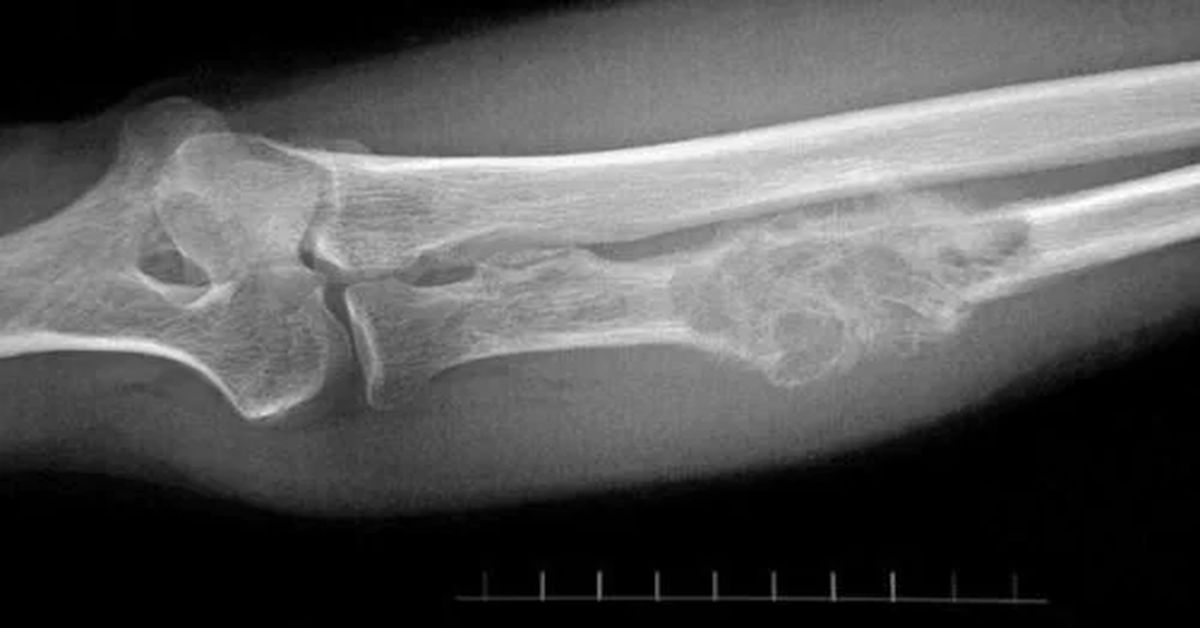

Enfekte bölgeye yakın lenf bezlerinde şişme meydana gelebilir. Bu genellikle vücudun enfeksiyona verdiği yanıt olarak görülür. Bazı durumlarda enfeksiyonun olduğu bölgede kemik zayıflar. Sanki bir kırık varmış gibi şiddetli hassasiyet ya da deformite oluşabilir. Bu belirtilerden birkaçını yaşıyorsanız ve özellikle şiddetli kemik ağrınız varsa vakit kaybetmeden bir ortopedi veya enfeksiyon hastalıkları uzmanına başvurmanız önemlidir. Erken tanı ve tedavi, kalıcı hasarları önlemede hayati rol oynar.

Ciddi travmalar sonucunda oluşan açık kırıklar, kemiğin dış ortamla temas etmesine neden olur. Bu durumda bakteriler doğrudan kemiğe ulaşarak enfeksiyona yol açabilir. Özellikle toprak, paslı metal gibi kirli cisimlerle temas eden yaralanmalarda risk artar. Ortopedik ameliyatlar sırasında kullanılan protezler, vidalar veya çiviler nadiren enfeksiyon kaynağı olabilir. Ameliyat bölgesine yeterli sterilizasyon sağlanmadığında ya da bağışıklık sistemi zayıf olan bireylerde mikrop kapma ihtimali artar.